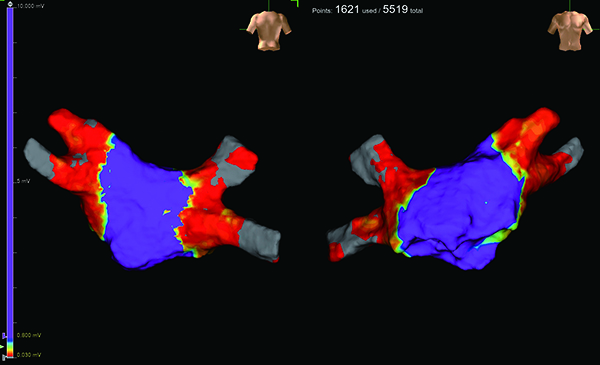

左心房を描出した画像では、パルスフィールドアブレーションを終えた低電位領域が赤、洞結節の制御下にある高電位領域が紫で示され、肺静脈隔離の成功を確認できます。このプロセスは高周波アブレーション治療でも同様です。

3Dマッピング画像

(パルスフィールドアブレーション治療後)

左心房と4本の肺静脈で左が正面から、右が背面から描出したもの。赤は低電位領域、紫は高電位領域を示す。きれいに肺静脈が隔離されており、肺静脈内から異常信号が出ても左心房には伝わらなくなっている